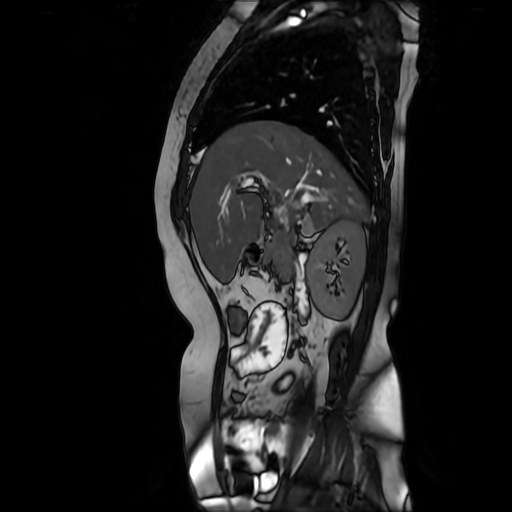

HISTORIA DEL PACIENTE

Paciente de sexo femenino, de 56 años de edad, refiere dolor en cuadrante superior derecho, indica que le realizaron colecistectomía de hace mas o menos 7 años, presenta cuadro de ictericia de 6 meses de evolución. Médico tratante le solicita estudio de Resonancia de vías biliares (Coilangioresonancia)

Se prepara a paciente previo a ingreso a zona 4 del área de resonancia magnética, paciente se presenta con catéter en región anterior del antebrazo, se utiliza bobina de abdomen de 16 canales y se procede a obtener localizadores en los tres planos, para luego adquirir imágenes en diferentes planos, en secuencias espin echo, eco de gradiente, secuencia de difusión. Se utiliza medio de contraste hepatoespecifico con dosis sugerida por fabricante.

HALLAZGOS IMAGENOLOGICOS

Se observa dilatación de las vías intra hepáticas a expensas de sus ramas hepáticas derecha, anterior y posterior, hepática izquierda y hepática común. El hepático común da la apariencia de estar anastomosado a un asa de intestino, lo que sugiere la posibilidad de una cirugía entero biliar.

No se logra observar el colédoco.

1. Dilatación de vías biliares intrahepáticas

2. Anastomosis entero biliar

3. Colangitis aguda